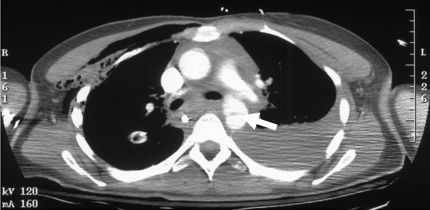

Компьютерная томография стала стандартным исследованием в диагностике разрыва аорты. Ее преимущества перед другими сложными методами исследования включают широкую доступность, скорость, чувствительность, разумную стоимость и простоту интерпретации. Признаками разрыва аорты являются утолщение стенки, выход контраста за пределы тени аорты, (парааортальная гематома), тромбы, псевдоаневризма.

Компьютерная томография. Формирование псевдоаневризмы

Чувствительность и прогностическая ценность компьютерной томографии близка к 100%.